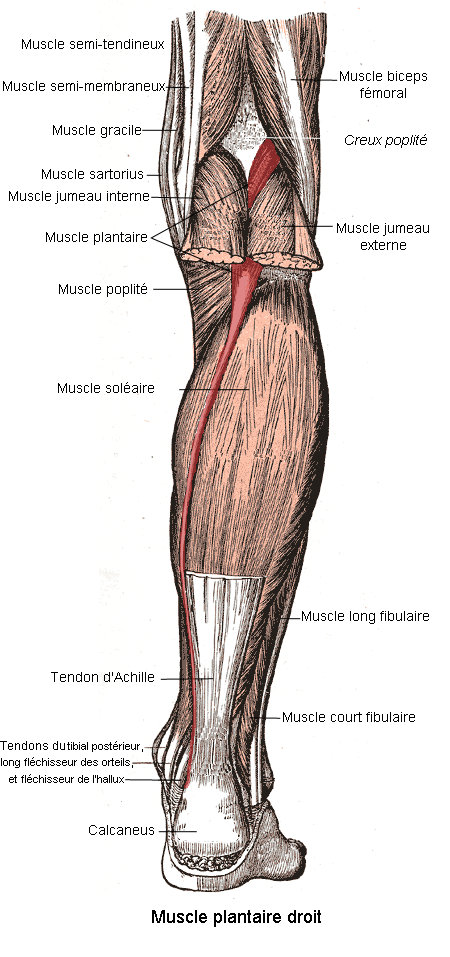

Анатомия подошвенной мышцы голени: подробное рассмотрение